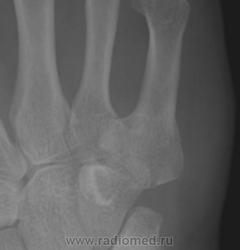

Точно такой-же локализации сесамовидных костей по Королюку не нашел, приблизительно такую локализацию имеет hamulus terminale(hamuli proprium, praesphenoid) №29 , но она там на много больше и вытянутая в проксимально-дистальном направлении. Так что склоняюсь к травматическому генезу этого образования.

Асептический некроз основания V пястной кости? Описывают же "раструбообразную деформацию" головки плюсневой кости при болезни Келлера, может быть здесь возникло нечто подобное. Костный фрагмент.